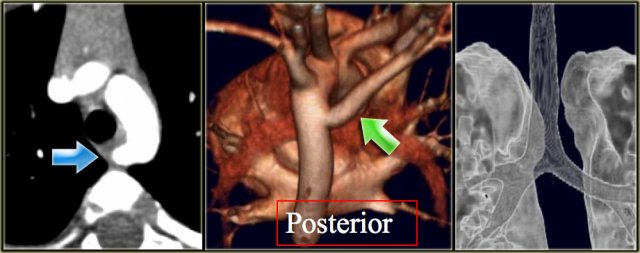

Double Arch with Atretic Segment Double Arch with Atretic Segment

On the left a dominant right arch and a small left arch.

The atretic segment is marked by the arrow.

Notice the four vessel sign.

On a posterior view the interruption is nicely demonstrated.

Remember that there is still a ring, so there is still obstruction.

Another case on the left.

Do not call this a right arch.

It still is a double arch and there is a atretic fibrotic segment on the posterior side of the left arch, that completes the ring.

Same patient.

Always look at the airways.

On the recoonstruction the impression on the trachea is better appreciated.